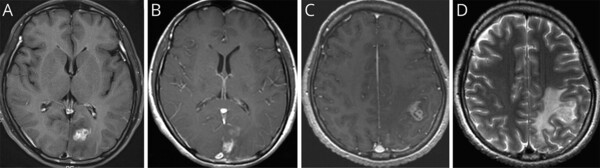

이번 연구는 서울대병원에 내원한 40대 여성 환자를 대상으로 이뤄졌다. 환자는 심한 두통과 구토 증세로 병원을 방문했으며, 초기 뇌 MRI에서 좌측 후두엽에 불규칙하게 조영된 종양성 병변이 발견돼 뇌종양이 의심됐다. 의료진은 수술을 권유했지만, 환자는 증상이 일시적으로 호전되자 치료를 거부하고 퇴원했다.

7개월 후 환자는 다시 극심한 두통과 전신 발작으로 병원을 방문했다. 후속 MRI에서 병변이 좌측 후두엽에서 좌측 두정엽으로 이동한 것이 확인됐고, 이 병변 이동은 스파르가눔증의 대표적인 진단 단서가 됐다.